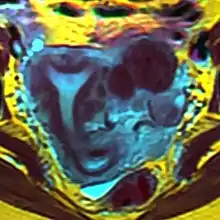

| Arcuate uterus (marked in red) seen on MRI | |

The arcuate uterus is a form of a uterine anomaly or variation where the uterine cavity displays a concave contour towards the fundus. Normally the uterine cavity is straight or convex towards the fundus on anterior-posterior imaging, but in the arcuate uterus the myometrium of the fundus dips into the cavity and may form a small septation. The distinction between an arcuate uterus and a septate uterus is not standardized.